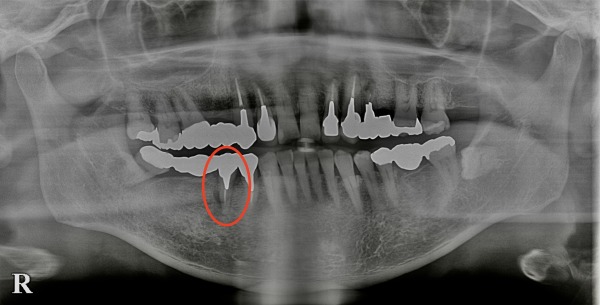

初診時のレントゲン写真がこちらになります。

右下にブリッジが入っており、その支えとなっている右下5番目の周囲の歯茎に腫れを認めておりました。

右下5番目の歯の周囲の歯周ポケットを調べると8mm程度の深さがありました。正常は3mm以下ですので、かなり深い歯周ポケットがあり、歯周病の状態であることが分かりました。

この歯は過去に根管治療(神経を取る治療)を受けていた上に、ブリッジの支えとして通常以上の過剰な力がかかり続けていたため、歯根破折(歯の根にヒビが入ること)をしている可能性を疑いました。

歯根破折を確認するためにブリッジを外し、マイクロスコープで調べたところ、歯根破折していることが分かりました。残念ながら歯根破折してしまっている歯は残すことができませんので、抜歯をさせていただきました。